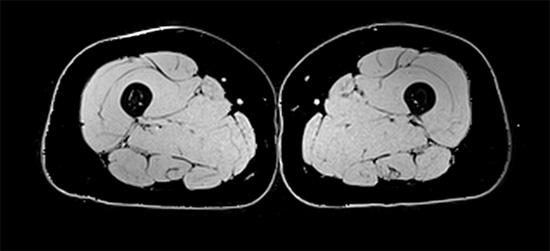

Muscle weakness and atrophy are common clinical phenomena observed associated with aging as well as following cast immobilization, bed rest, surgery, spaceflight, and injury or disease. For around two decades we have worked to better delineate the mechanisms underlying the loss of muscle and motor function that occurs as a result of both aging and disuse. This work has clearly indicated that the nervous system plays a critical role in both muscle weakness and fatigue resistance. For instance, our original work has indicated that reductions in neuronal excitability and motor unit function and firing rates, neuromuscular junction transmission failure, accelerated brain aging are key contributors to muscle weakness and mobility limitations associated with aging. We have observed similar findings in our highly  rigorous experimentally controlled studies of disuse. These contributions are important as the development of rationale and effective therapeutic interventions targeting restoration of muscle function necessitates an in-depth understanding of the neural and muscular mechanisms mediating muscle and motor function.